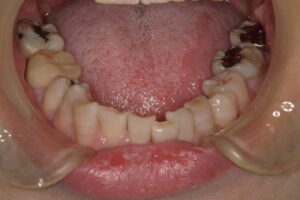

下の前歯にがたつきがあります。奥歯が内側に倒れています。向かって左の奥から3番目、4番目がわかりやすいですが、奥歯は全部そうなっています。舌が写っていますが、窮屈そうにみえます。前歯が並ばないことから顎が少し小さいこと、歯が内側に傾斜していることで、舌の置き場が狭いのです。舌は行き場をなくすと奥に行くか、下にいくしかありません。そうなると気道が狭くなります。人は呼吸しないと生きていけませんから気道を確保するために首を突き出すような姿勢をとります。姿勢が悪くなる原因となります。無理な姿勢を維持するので、適正な筋肉の使い方でなくなります。肩こり、首の凝り、腰痛など全身はつながっています。かみ合わせのズレや不正咬合から離れた部位に不具合が出現する可能性があるというのはこういうことなのです。